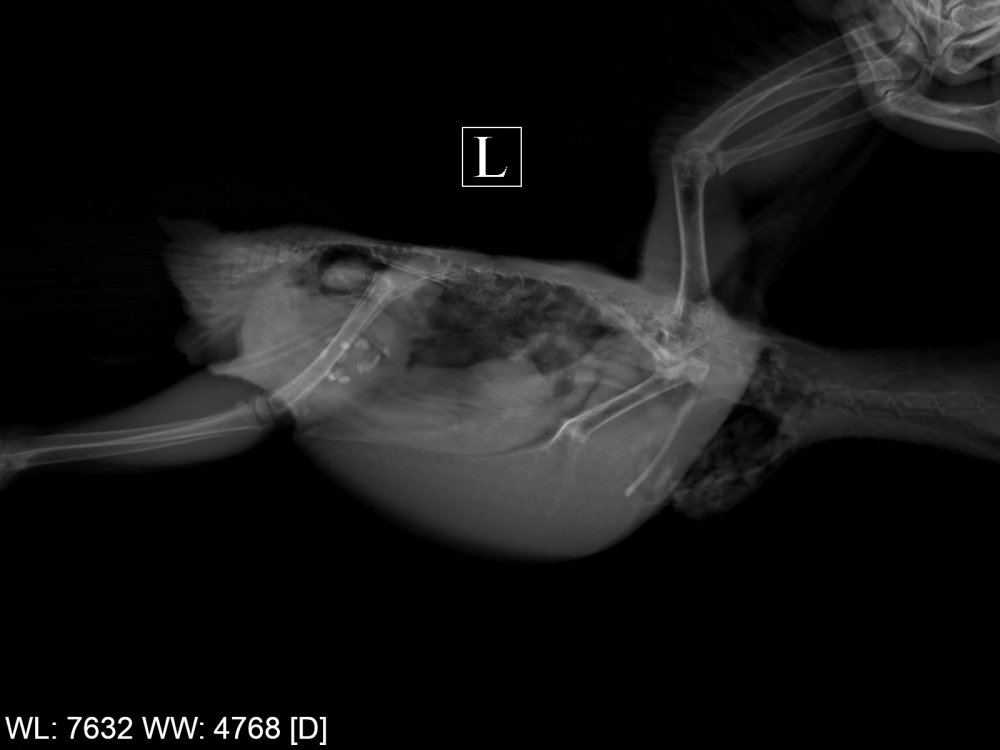

напомните пожалуйста рентген лёгких в двух проекциях не делали?

Да, рентген был в октябре, уже выкладывал. Ни от паразитов, ни глистогонку не делал.

@ната1805, ну, Рыжему уже 3 раза делали рентген, я всё тут выкладывал... Zosia смотрела, но ничего конкретного не сказала про лёгкие и воздушные мешки. Правда, чёткость рентгена не очень, но лучше в моей глуши, к сожалению, не сделать – не тот уровень оснащения.

@ната1805 Плохо. Повторный рентген – уже после курса антибиотикотерапии – очень плох:

.thumb.png.b862e04782aadef0209ef50f109bb175.png-.thumb.png.6edb55837bbb4c3f98b19626d986f64f.png

Разительные изменения, по сравнению с октябрьскими снимками: Zosia констатировала злокачественную опухоль правой почки, проблемы с сердцем (в т.ч. расширена левая дуга аорты), множественные гранулёмы в лёгких и новообразование в слизистой зоба. Всего этого не было на октябрьском и более ранних снимках. Может ли патологическое изменение почки на снимке быть не опухолью, а инфекционным воспалением – Zosia отвечать не стала. Видимо, не может.